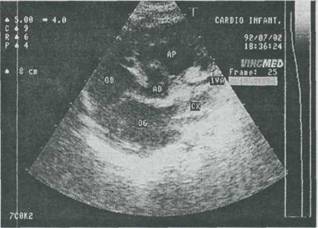

Fig. 9-27. Anomalie de origine a arterei coronare la un sugar cu cardiomegalie si insuficienta cardiaca. Echocardiografie 2-D. Artera coronara (IVA) ia nastere din artera pulmonara.